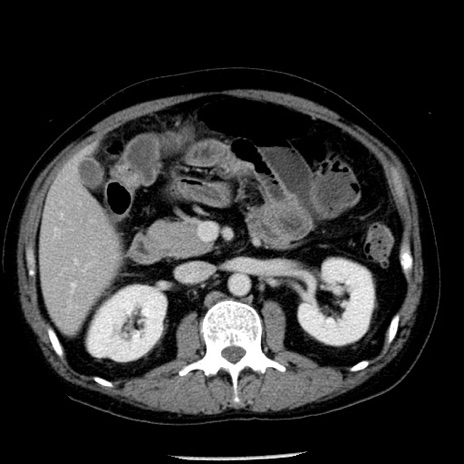

冠状断像

【症例】40歳代男性

【現病歴】2日前から胃痛あり。徐々に周期的な激痛に変化した。本日になっても激痛があるため受診。

【身体所見】意識清明、BT 38-39℃台あり、腹部:膨満、やや硬、右下腹部に圧痛あり。

【データ】WBC 8500、CRP 23.26